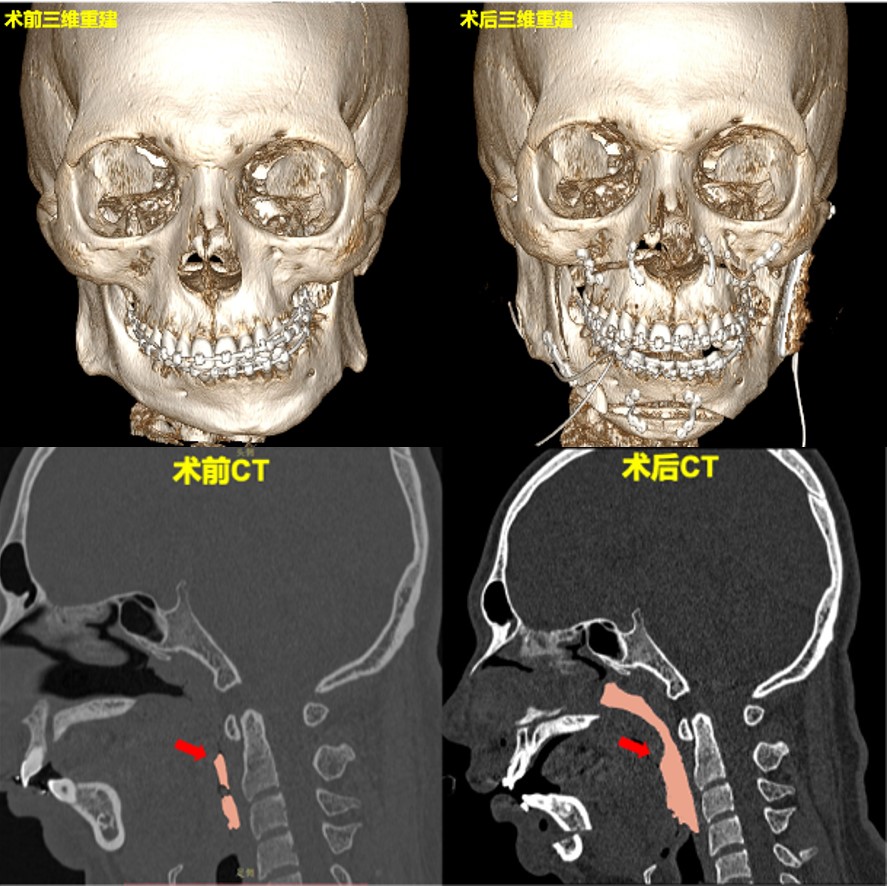

手术团队应用三维CT重建、虚拟设计与3D打印个性化钛板技术,对患者的颌骨畸形、咬合关系及气道变化进行了综合评估。通过数字化模拟,术前即可实现上下颌骨位置关系、关节位置及咬合关系的精确预测与验证,为复杂的手术提供了科学、可控的方案支持。

术后,患者自觉通气顺畅,睡觉时无憋气,家属诉患者打鼾明显缓解。检查可见面部对称性良好,关节运动正常,咬合关系稳定。螺旋CT显示,气道显著扩张。

患者面部畸形、呼吸道狭窄在术后得到明显改善